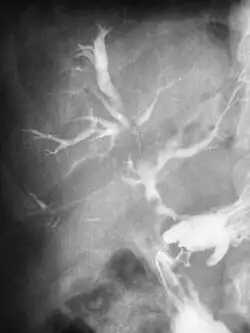

- Gallenfistel: von der Gallenblase bzw. den extra- oder intrahepatischen Gallengängen ausgehende innere oder äußere galleführende Fistel. Einteilung: als äußere G. mit Mündung an der Körperoberfläche (Fistula biliocutanea) oder in innere Organe, z. B. die Bronchien (Fistula bronchobiliaris) oder als innere G. (Fistula biliodigestiva), bei der eine Verbindung zwischen Gallengangsystem bzw. Gallenblase und Magen oder Darm besteht. Ätiol.: spontane äußere G. postoperativ, infolge Nahtinsuffizienz oder nach Entfernung einer Gallengangsdrainage; eine operativ angelegte äußere Entlastungsfistel, z. B. als Drainagefistel (Gallenblasendrainage). Spontane innere G. nach erfolgter Gallenwegeperforation (z. B. Gallenblasenperforation) durch Steine, nach Durchbruch eines Duodenalulkus oder posttraumatisch; außerdem künstliche (operativ angelegte) innere Entlastungsfistel zur Galleableitung in Magen oder Dünndarm (= biliogastrische bzw. biliointestinale Anastomose). Kompl.: bei innerer G. v. a. Schrumpfgallenblase mit chronisch rezidivierender Cholangitis, bei äußerer G. z. B. Osteoporose, gestörte Fettresorption, Elektrolytverlust.